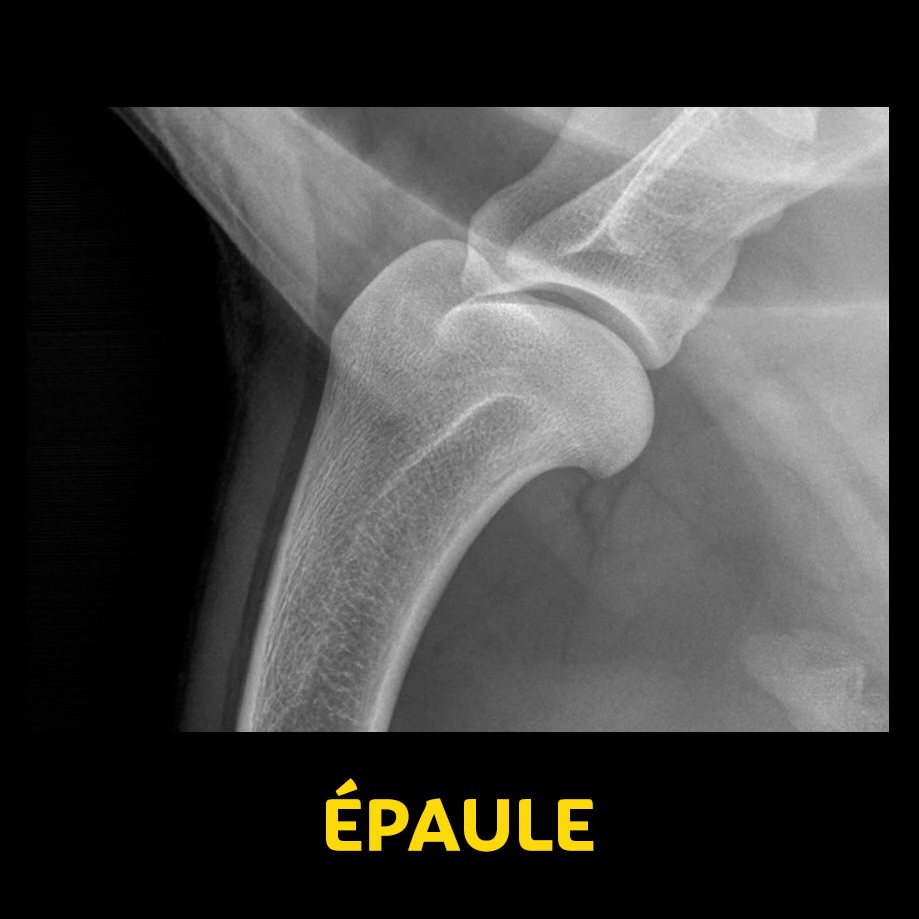

- En latéral (Tête, colonne, épaules, thorax, abdomen, bassin)

- Portion rostrale ou crâniale à la gauche de l’écran

- Portion caudale à droite de l’écran

- En Ventro-dorsale / Dorso-ventrale (Tête, colonne, épaules, thorax, abdomen, bassin)

- Rostral ou crânial vers le haut de l’écran

- Caudal au bas de l’écran

- Droite de l’animal à gauche de l’écran

- Gauche de l’animal à droite de l’écran